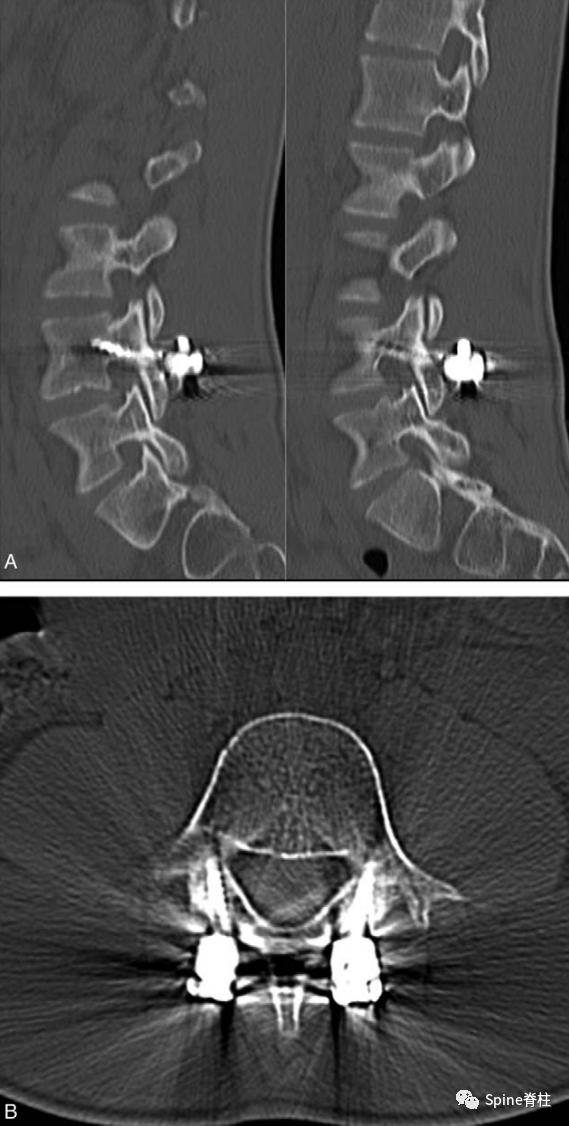

峡部裂的CT分型 :A=早期(线性骨折),B=进展期(明显的骨间隙),C=终末期(假关节形成)

右侧为进展期峡部裂,左侧为早期峡部裂,右侧图片是支具固定7个月后愈合